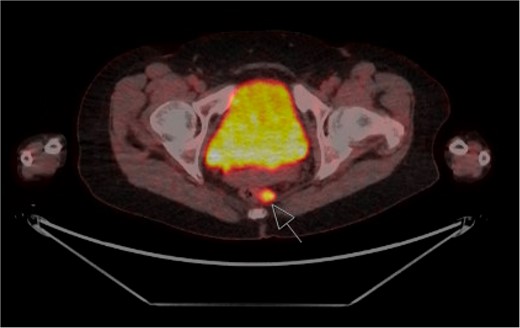

The patient was staged with a magnetic resonance imaging (MRI) brain and fluorodeoxyglucose-positron emission tomography (FDG-PET) scan which identified several prominent FDG-avid mesorectal lymph nodes concerning for regional disease, with no evidence of distant metastases (Fig. 2). Due to the rarity of the presentation, the case was presented at both colorectal and melanoma multi-disciplinary team meetings. The consensus decision was to proceed to an APR for management of the loco-regional disease. The APR histopathology confirmed Stage 2 disease, with 2/18 lymph nodes involved. There was no residual invasive disease at the site of previous resection, however, a 4 mm submucosal aggregrate of melanophages at the tumour bed was found. The patient recovered well post-operatively and was referred to medical oncology for systemic treatment.

FDG-PET staging scan with enlarged FDG-avid mesorectal lymph nodes (arrow).